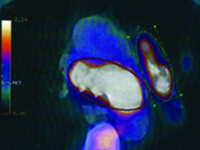

Myxomas of the heart are the most common primary heart tumors. The incidence of this condition is estimated at 5/million/year. The recommended treatment is to resect the tumor as soon as possible, along with a margin of healthy tissue. Myxomas can recur if all tumor cells are not removed during surgery.